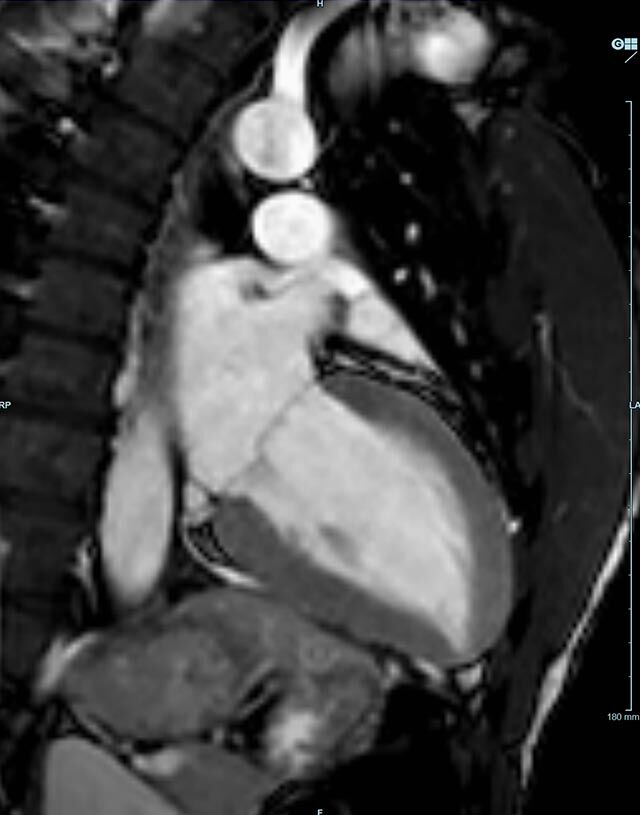

- kardiale Ischämiediagnostik mit medikamentöser Stress-MRT (Adenosin)

- Infarktnarbendarstellung/Vitalität

- Kardiomyopathien (z.B. Myokarditis, DCM, HCM/HOCM, Amyloidose, Sarkoidose)

- Klappenbeurteilung mit Phasenkontrastangiographie

- Tumoren Herz und Mediastinum

- Fehlbildungen

- MR-Angiographie zur Erfassung und Verlaufskontrolle von Aneurysmen der Aorta thorakalis und ihrer Gefäßabgänge